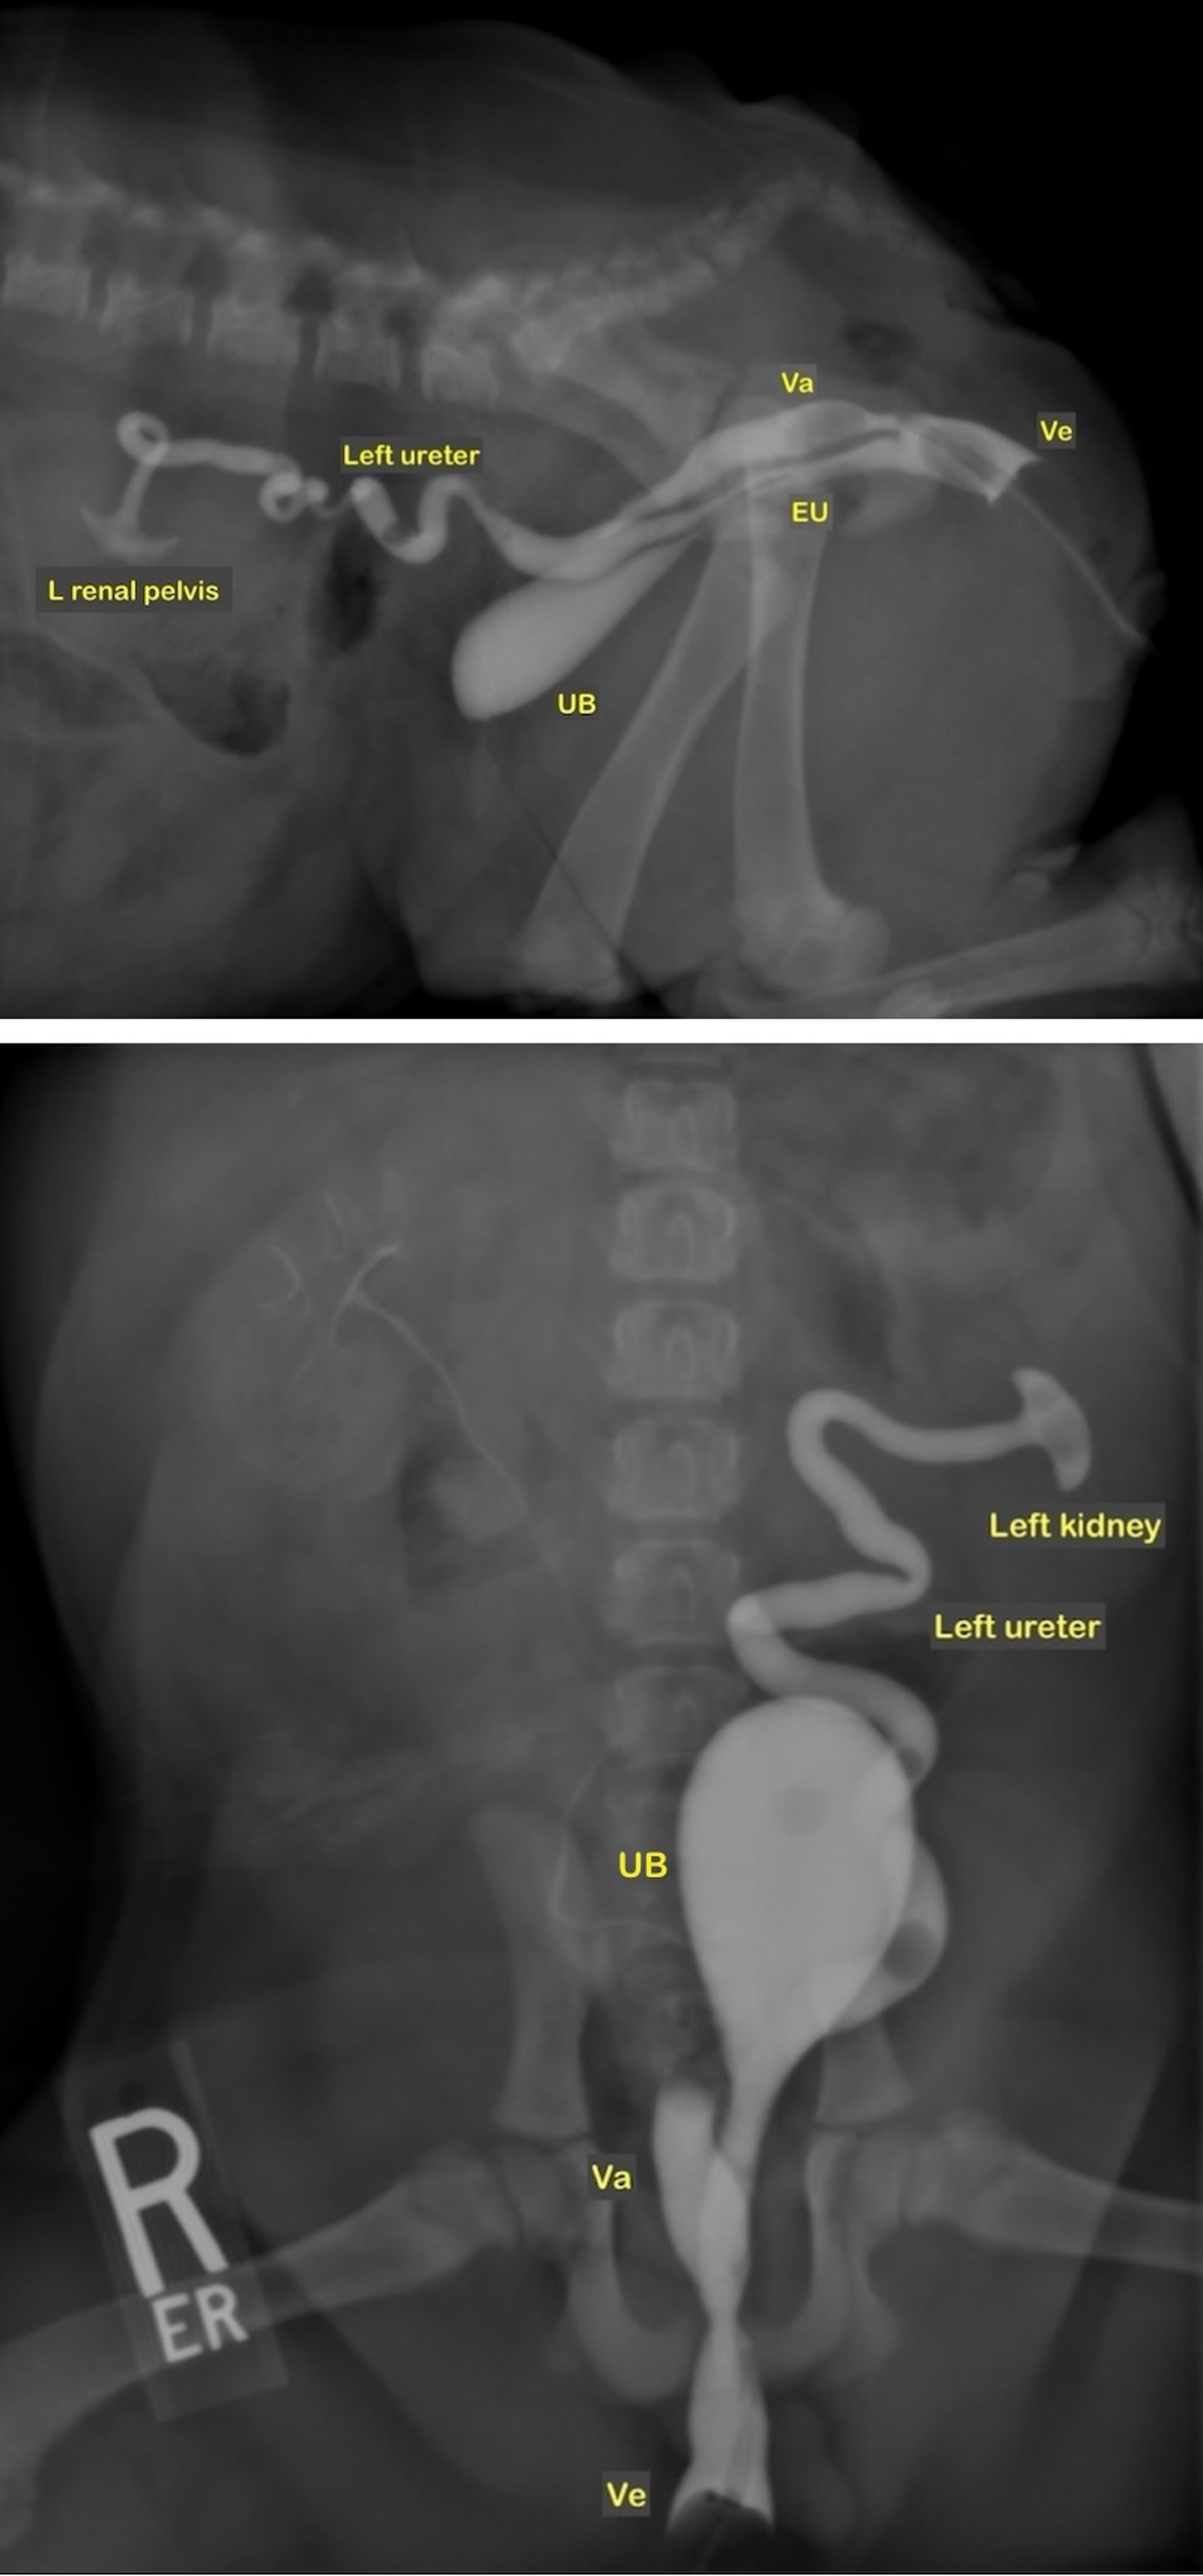

Uréter ectópico, hembra de bulldog inglés

Imágenes fluoroscópicas de una vaginocistouretrografía retrógrada que muestran renomegalia izquierda, ureteromegalia izquierda y un uréter ectópico izquierdo en una hembra de bulldog inglés con incontinencia urinaria. En la vista lateral, el uréter ectópico izquierdo dilatado es dorsal a la uretra y confluye con la uretra caudalmente a la vejiga de la orina. La pelvis renal y el uréter derechos son normales. EU: uréter ectópico que se une a la uretra; UB: vejiga urinaria; Va: vagina; Ve: vestíbulo.